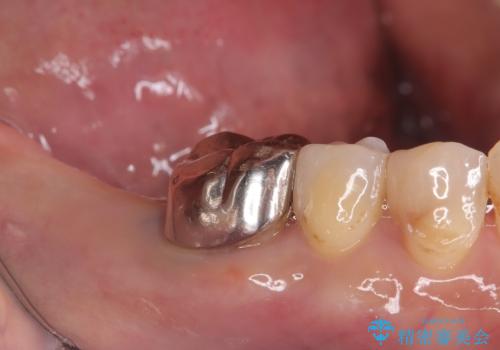

- 患者様は、右側の奥歯でしっかり噛めないことを主訴に来院されました。診察の結果、右上6・右下6の根管治療が不十分で、感染のリスクがある状態と判断。これらの歯は再根管治療を行い、セラミッククラウンで補綴することにしました。また、右上7・右下7は欠損しており、噛み合わせを回復するためにインプラント治療を計画しました。

まず、右上6・右下6の根管治療を再度行い、根の状態をしっかり整えた上で、セラミッククラウンを装着しました。さらに、欠損していた右上7・右下7にはインプラントを埋入し、セラミッククラウンを装着。治療後は、「奥歯でしっかり噛めるようになり、不安なく食事ができるようになった」と患者様にも大変ご満足いただきました。